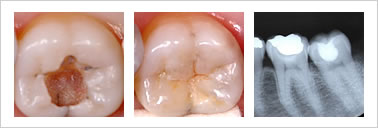

虫歯とは、虫歯を作る細菌が、甘いものを原料にして、酸を作り、歯を溶かして穴を開けたものです。

穴の大きさによって、C1~C4まで4段階に分けられます。

それぞれの段階に応じて、治療の仕方が異なります。

C2の治療

歯のエナメル質を通過して、中間層の象牙質まで穴が開いたものです。この段階でも、はじめのうちは、痛みを感じません。しかし、進むにつれて、まず冷水痛やチョコレートなどの甘いもので痛みを感じるようになります。虫歯は徐々に進行しますから、痛みを感じなくなったからといって、放置するのはきわめて危険です。

この段階での治療は、大きく2つのパターンに分けられます。